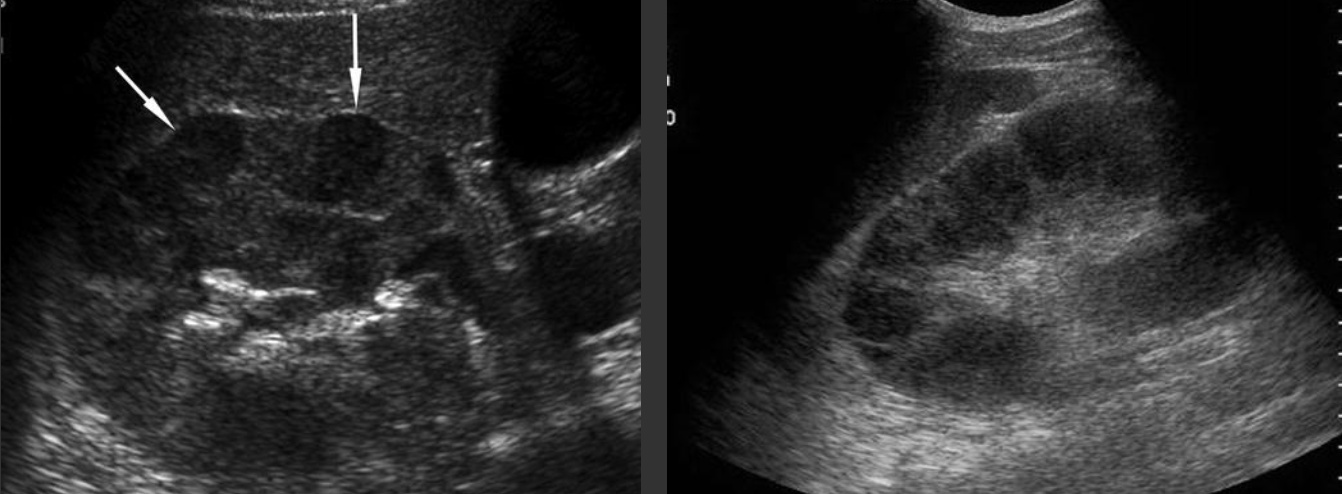

Simple Renal Cyst → common lesion of kidney, fluid-filled sac (benign, Bozniak 1)

clinical hx: incidence increases with age (50+), uncommon in children

s/sx: asymptomatic

2D US: anechoic, well-defined smooth, thin wall, round or ovoid, posterior enhancement

color doppler: avascular

DDX: complex cyst

Complex Renal Cyst → any cyst that is not a simple cyst

clinical hx: post-surgery, trauma

s/sx: flank pain, fever, hematuria, WBC increase, can be asymptomatic

2D US: well-defined cystic structure, internal echoes or anechoic, septations, focal hypoechoic inner mural extension, can be hemorrhagic

color doppler: if solid can have vascularity

DDX: malignant tumor, RCC